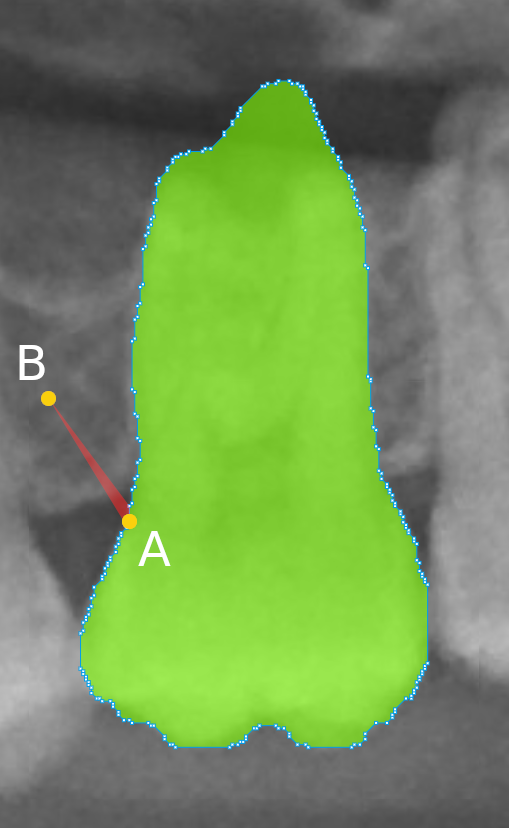

Refer to caption

(a) Original code.

(b) Changed code.

Figure 5: Illustration of the software visualization due to the code changes. The red area evinces the higher impact in the annotation when on a point shift. We reduced the shape opacities, easing the annotation verification, and lowered the number of control points. (a) Visualization of a tooth annotation with the original code and no tolerance in the Ramer–Douglas–Peucker algorithm and the impact on the annotation when point A moves to point B. (b) Visualization of a tooth annotation with the changed code and the impact on the annotation when point C moves to point D.

The HITL-based labeling started with the predictions of the HTC neural network. We labeled 450 radiographs in the first HITL iteration, as indicated in Figure 4. This iteration was considered experimental, as the annotators had not previously verified annotations from model predictions. Indeed, it quickly became notorious that manual image labeling is quite different from labeling verification. When labeling a radiograph from scratch, the annotator may promptly detect or localize the teeth and segment their instances using the annotator software mechanisms such as the polygon or brush tools. In the COCO Annotator software, the resulting area is filled with a colored layer to distinguish the already segmented objects from the others. On the other hand, when working on verifying neural network predictions, the human annotators must visually inspect the results and quickly confirm or correct the provisional labels. For that, the annotators can benefit from any software annotation tools, but in our case, they most frequently used the polygon point drag-and-drop feature. Two issues arise from this: (i) the filled segmented areas obstruct the instances, hampering the verification; (ii) the large number of points per segmentation slows down and hardens the corrections because point shift has less impact on the annotation. We mitigated these issues by changing the software source code, reducing the shape opacity, and lowering the number of control points through the Ramer–Douglas–Peucker algorithm with a tolerance of 2 pixels (Douglas and Peucker, 1973). Figure 5 illustrates these modifications, evincing the new higher impact of point shift. Furthermore, we added a keyboard shortcut to toggle the annotation visualization, which was very helpful for the annotators.